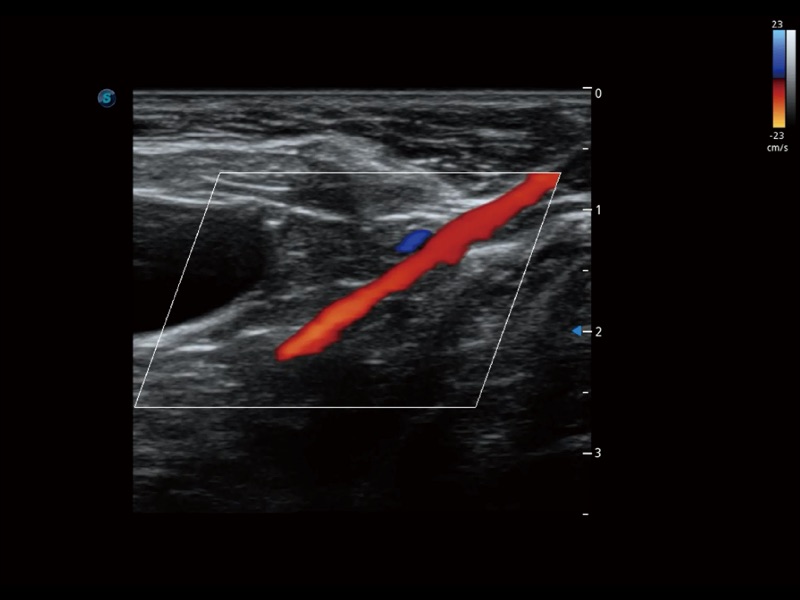

(犬)髂动脉血流

优异的基础图像

ProPet 70 全新的动物超声智能软件和丰富的探头群,为动物医生提供了高清晰度和精细分辨率的图像,无论在宠物、马科、畜牧还是实验室动物等应用中都可以轻松应对,为您的日常工作带来满意的体验。